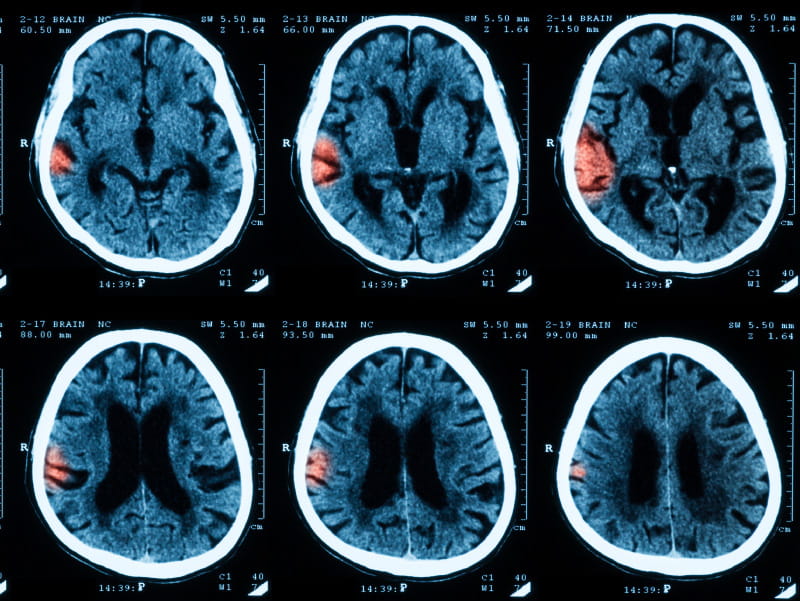

29+ What Happens To The Brain During A Stroke Images. Some even call it a brain attack. that might sound like a bad zombie movie, but what's happening is part of your brain isn't getting enough blood. Why does a stroke cause brain damage so quickly and why is it a problem to delay medical care?

The internal carotid arteries form the anterior (green) circulation and the vertebral. Communicating may be difficult if stroke causes aphasia, a condition that results when areas of. Stroke or cerebrovascular accident (cva) is the clinical designation for a rapidly developing loss of brain functions due to a disturbance in the blood vessels supplying blood to the brain.

Stroke or cerebrovascular accident (cva) is the clinical designation for a rapidly developing loss of brain functions due to a disturbance in the blood vessels supplying blood to the brain. What happens to the brain during a stroke? Introduction what is a stroke? Every two seconds, someone in the world has a stroke.